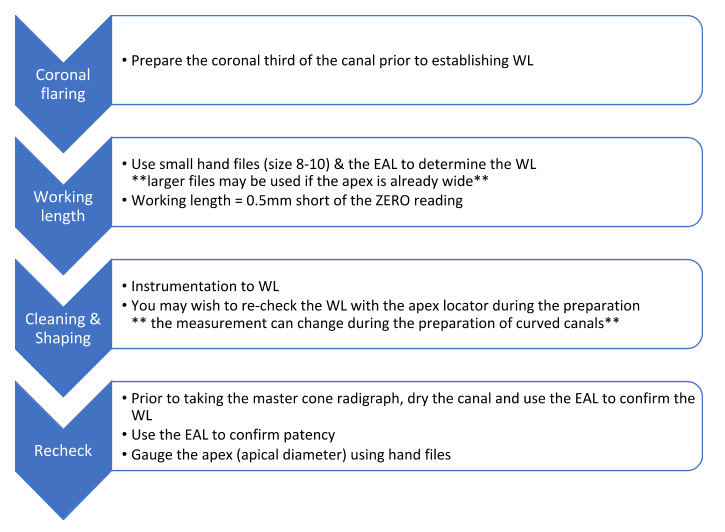

My protocol

I keep the apex locator connected and use it throughout the cleaning & shaping procedure.

Coronal flaring

I recommend flaring the coronal third of the canal prior to trying to determine the working length.

The zero reading is the only accurate measurement produced by the apex locator. The visual scale bar leading to the zero reading does not accurately represent where the file lies within the canal.

However, this scale is helpful to check the reading is stable and moves in tandem with the file movements. If the zero reading flashes erratically then the reading is not accurate.